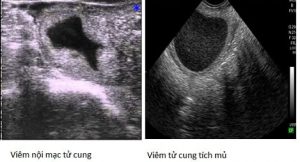

Bên cạnh việc chẩn đoán có thai sớm, và chính xác hơn so với phương pháp truyền thống là khám qua trực tràng. Với kỹ thuật siêu âm, người ta có thể chẩn đoán chính xác bào thai còn sống hay đã chết, thông qua việc quan sát tim thai đập. Với phương pháp khám bằng tay, chỉ xác định có thai hay không, còn không thể xác định được bào thai còn sống hay đã chết, ở giai đoạn đầu của quá trình mang thai. Cuối cùng, trong chẩn đoán có thai sớm ở bò, thì dùng siêu âm còn phân biệt được trường hợp, là có thai với viêm nội mạc tử cung tích dịch, tích mủ, làm cho tử cung cũng căng lên, khi khám bằng tay dễ nhầm lẫn là có thai. Tuy nhiên, dùng phương pháp siêu âm, thì trường hợp này phân biệt rất dễ dàng, bằng việc xác định tử cung có bào thai hay không.

Xác định bệnh lý bên trong tử cung

Thông qua siêu âm, cũng dễ dàng phát hiện các bệnh lý ở tử cung như: viêm nội mạc tử cung, viêm tử cung tích mủ, tích dịch,…Bởi lẽ, viêm trong tử cung, thường tạo ra các xoang phồng lên bên trong, nếu tích dịch sẽ hiển thị lên màn hình siêu âm với màu đen. Còn khi, bên trong tử cung tích mủ, hình ảnh siêu âm sẽ cho màu trắng, bên trong xoang tử cung giãn rộng.